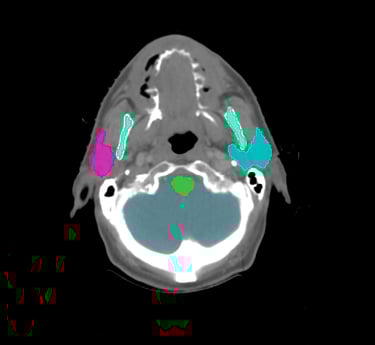

Head & Neck

Choose from a combined structure volume including BrainStem, Brain, Chaism, Mandible, Optic nerves Trachea and many more, or choose individual split sub-levels.